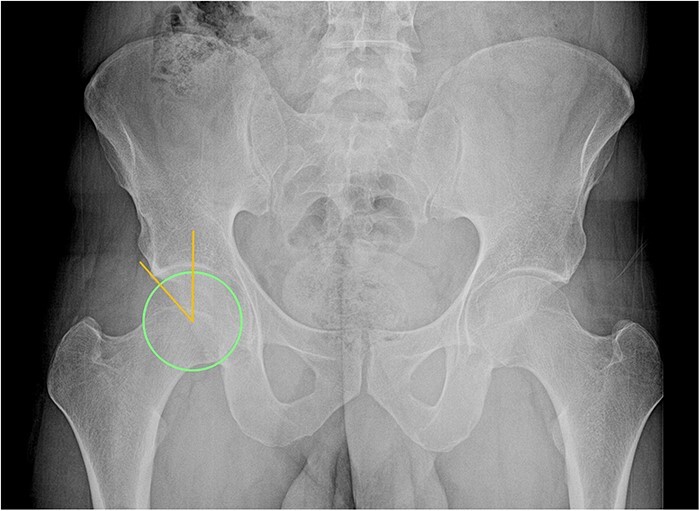

股髋臼撞击综合征(FAIS)是髋关节的一种常见疾病,可对关节造成严重损害,导致退变和骨关节炎。FAIS是股骨头颈交界处与髋臼缘之间的异常动态接触,由一个或两个部位的骨形态改变引起。撞击部位的重复性创伤会对髋臼唇、软骨唇交界处和关节软骨造成进行性损伤。基于患者症状、特定临床体征和影像学表现的正确诊断将指导治疗并最终保留原有髋关节。FAIS患者的常见症状包括疼痛、咔嗒声、卡住、屈曲、僵硬、让位和髋关节活动范围有限。具体的临床操作可以帮助诊断,如屈曲内收内旋和屈曲外展外旋试验。影像学诊断包括髋关节和骨盆的正交x线片,以及磁共振成像/磁共振关节成像。FAIS的初始治疗可以是保守治疗,包括物理治疗、关节内注射和活动调节。目前,首选的手术治疗包括髋关节镜检查,其目的是纠正骨骼异常,修复或重建唇部病变,并根据需要处理其他关节内和关节外的紊乱。

Femoroacetabular impingement syndrome (FAIS) is a common condition of the hip that can cause significant damage to the joint, leading to degeneration and osteoarthritis. FAIS constitutes an abnormal and dynamic contact between the femoral head-neck junction and the acetabular rim, resulting from altered bone morphology at one or both sites. Repetitive trauma at the site of impingement generates progressive damage to the acetabular labrum, chondrolabral junction, and articular cartilage. Proper diagnosis based on patient symptoms, specific clinical signs, and imaging findings will guide treatment and ultimately allow preservation of the native hip joint. Common symptoms in patients with FAIS include pain, clicking, catching, buckling, stiffness, giving way, and a limited range of motion of the hip. Specific clinical maneuvers can aid diagnosis, such as flexion adduction internal rotation and flexion abduction external rotation tests. Imaging diagnosis includes orthogonal hip and pelvis X-ray views, as well as magnetic resonance imaging/magnetic resonance arthrogram imaging. Initial treatment of FAIS can be conservative and include physical therapy, intra-articular injections, and activity modification. Currently, the preferred surgical management consists of hip arthroscopy, which aims to correct bony abnormalities, repair or reconstruct labral lesions and address other intra-articular and extra-articular derangements as needed.